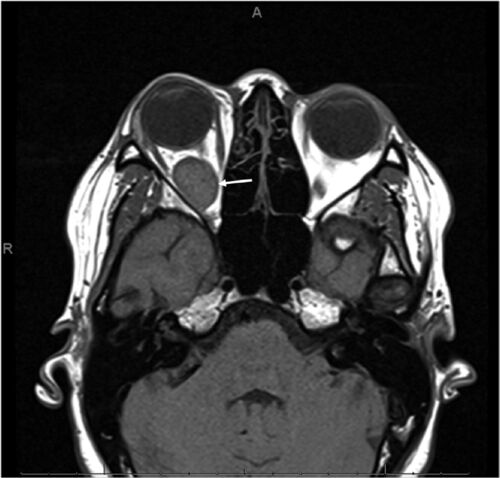

症例102:右眼後部痛と眼球突出により受診した妊娠28週妊婦(J Am Coll Emerg Physicians Open. 2020 Dec 31;2(1):e12340.)

病歴/身体所見 ・22歳(妊娠28週) ・重度の右眼窩後部痛と右眼球突出のためER受診 ・これまでに特に既往はなかった ・診察では眼球突出以外に神経学的異常なし ・視力以上なし、眼球運動により疼痛が誘発された 検査 ・CTおよびMRIにて1cmほどの眼窩内腫瘤…